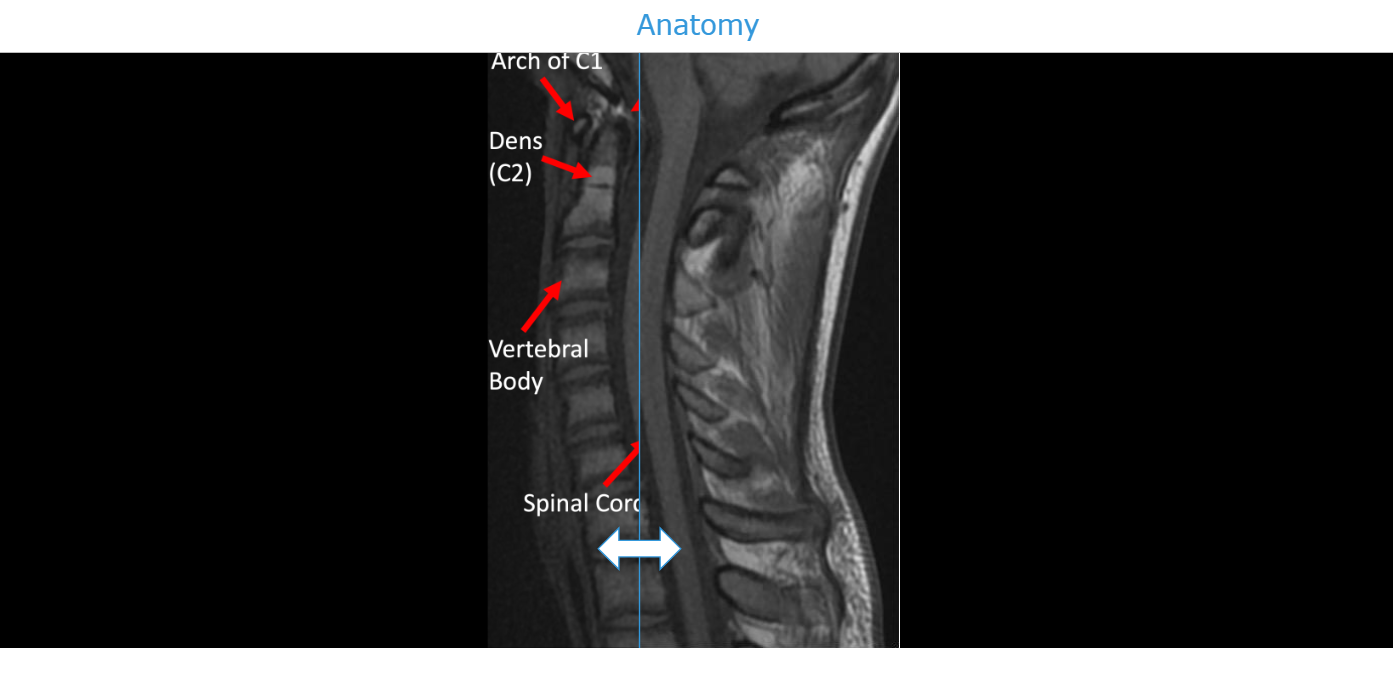

Make labeling exercises more engaging with interactive Before/After sliders. Students can explore images step by step, revealing names, labels, or key details, which reinforces visual learning and terminology retention. This flexible tool works for anatomy, geography, science, art, and other subjects, turning traditional labeling activities into dynamic learning experiences that boost student engagement.